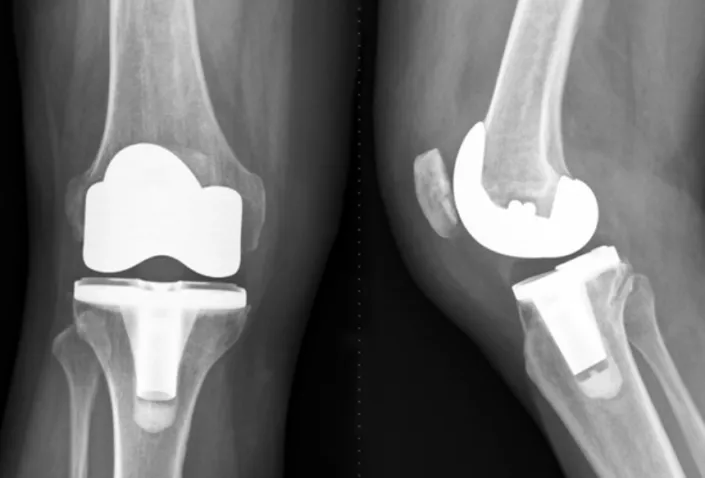

人工膝關節置換 之併發症 後遺症 建議與治療 – 松山景能物理治療所

2025/10/22患者需要與醫生或物理治療師進行詳細的討論,選擇最適合自己的手術方式。